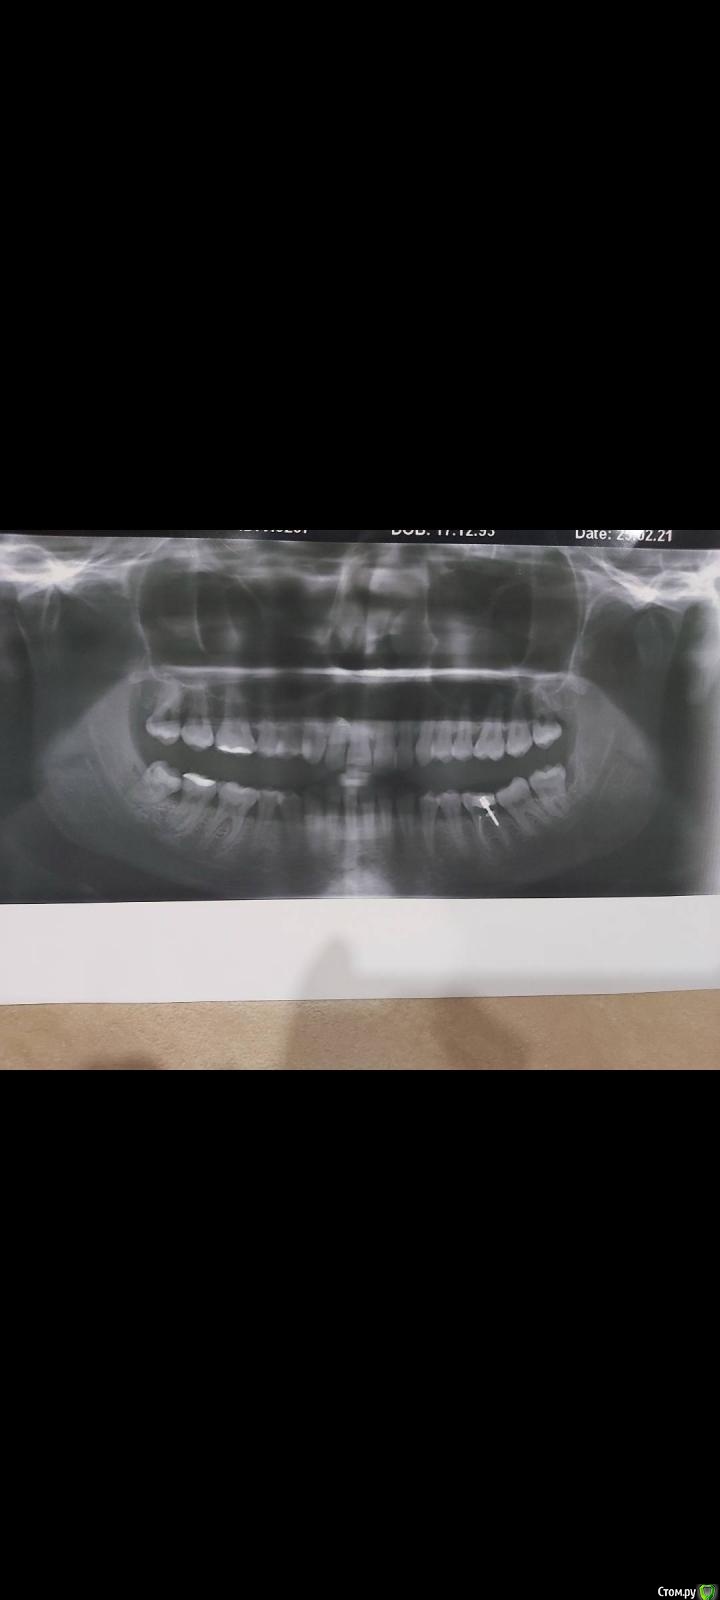

1223 Опубликовано 7 марта, 2021 Поделиться Опубликовано 7 марта, 2021 Здравствуйте.Не с первого раза посещения стоматолога поставили диагноз -хронический пародонтит, теперь одолевают сомнения о плане лечения.Подскажите пожалуйста, всё ли верно и все ли процедуры обязательны в моём случае? Ссылка на комментарий

сирена Опубликовано 10 марта, 2021 Поделиться Опубликовано 10 марта, 2021 Лазер - не обязательная процедура.Зубы мудрости я бы удалила. Ссылка на комментарий

St. Опубликовано 12 марта, 2021 Поделиться Опубликовано 12 марта, 2021 Проф. гигиена и закрытый кюретаж - нужны точно.Про необязательность лазера поддерживаю 100% 2 Ссылка на комментарий